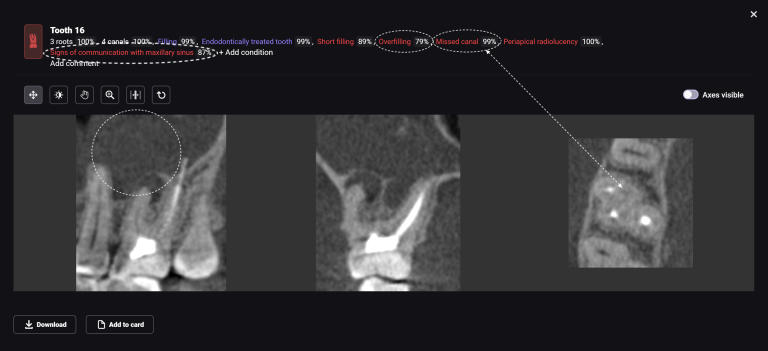

Solution: The automated process of segmentation and formation of 3D models from DICOM files allows extracting individual structures for subsequent 3D printing. The printed model of the third molar, taken from the “STL” module of Diagnocat, is used to prepare the socket for the transplanted tooth. The 3D reconstruction generated using Diagnocat displays the structure of the jaws and teeth and enables the visualization of tooth 37 (Universal 18) with periapical lesion around the roots. In this case, Diagnocat serves as a communication tool that helps convince the patient of the importance of timely implementation of the proposed treatment plan.